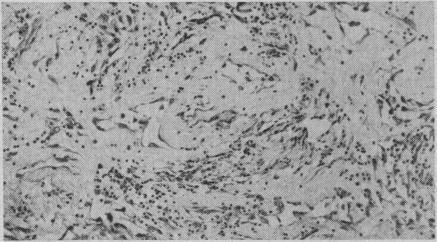

Lymphangiosarcoma in lymphoedema.

Can Med Assoc J. 1957 Mar 15;76(6):475-7.